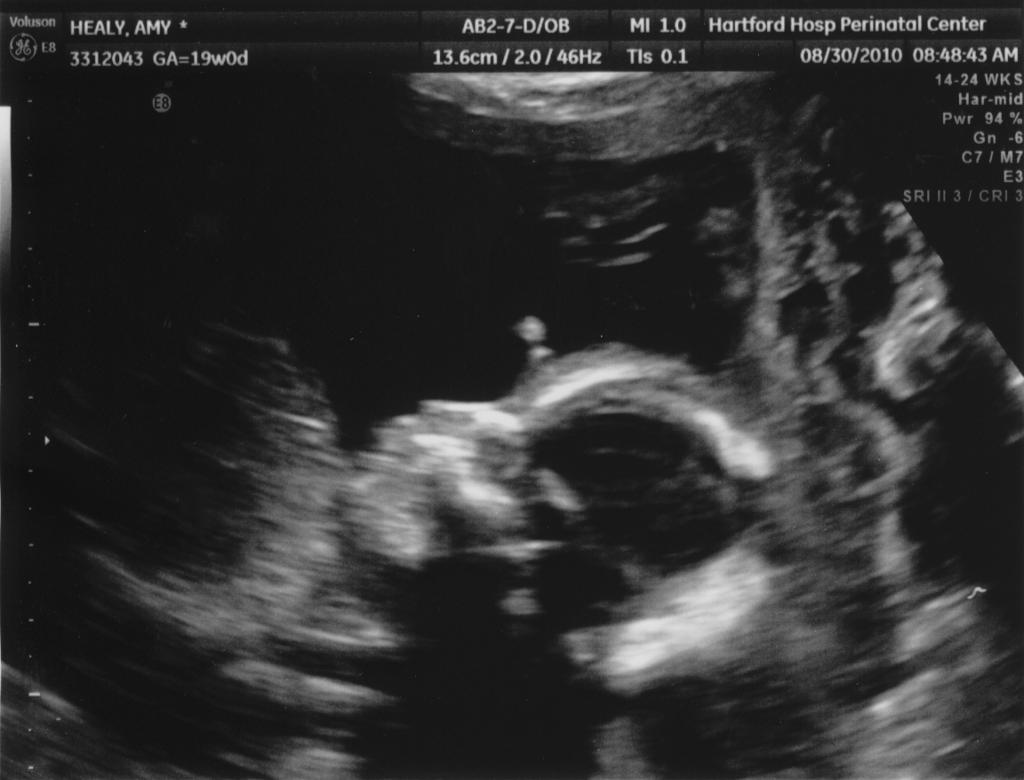

Well, it is a little embarrassing that it has been almost six months since our last real update to the blog! As most of you know, I am pregnant - we are expecting baby boy #2 on January 18. My energy level has been very low, or at least in the evenings when I would normally write blog updates. So, while many fun and exciting things have been going on, I have been very bad about documenting them.

The other exciting news is that we got a new car - traded in the old Subaru Forester for a Mazda 5 - a car with just a bit more room that we can fit two carseats in. So, with the big projects taken care of, we are focusing on getting all the little things ready for the new baby and on spending as much time with Seth as we can before things get shaken up a little with our new arrival. Seth has nicknamed his baby brother Tomato (sometimes Tomato Chicken Healy), and likes to kiss my belly and talk about how he will help Tomato when he is born. We know it will be a big adjustment, but we are very excited.